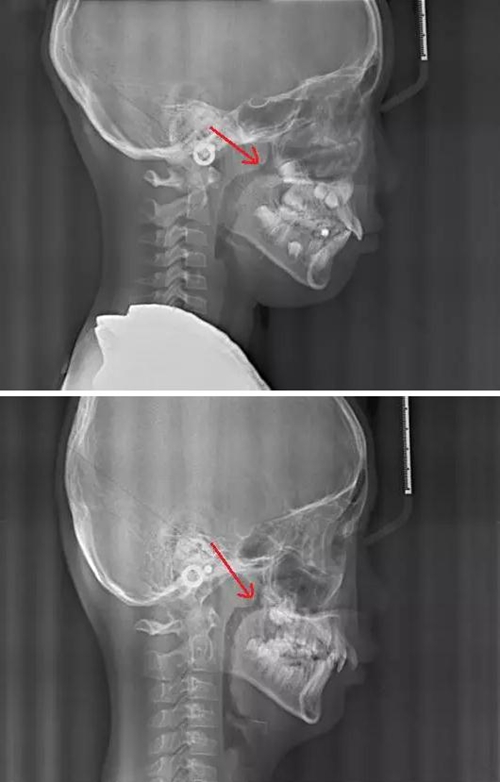

最后我們來對比一下正常的腺樣體和扁桃體的形態(tài)及位置,我們可以看到,正常的腺樣體和扁桃體在同一個位置形態(tài)的差異。

3.jpg